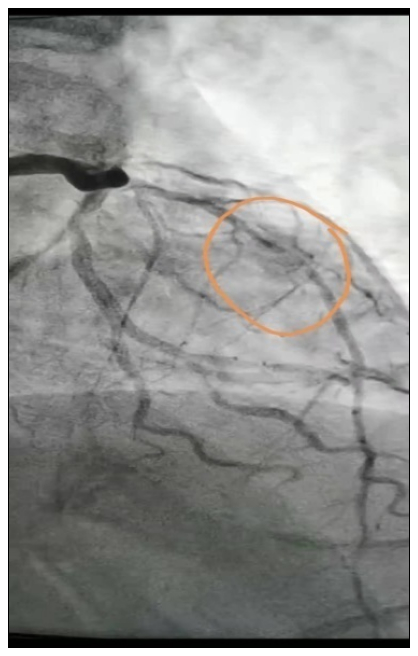

胸痛中心医护人员已提前做好术前准备,立即行DSA造影检查,术中见患者心脏冠脉前降支几乎闭塞,病情危重,急诊行经皮冠状动脉介入(PCI)手术,术后病人恢复良好,现已完全康复出院。